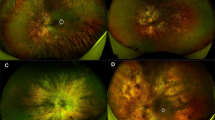

FAF and MP analyses

Blue-light FAF images were obtained by the same Spectralis HRA2 + OCT device (Heidelberg Engineering; Heidelberg, Germany). We developed an in-house tool to perform FAF intensity quantification based on the same ETDRS-9 sectors grid. A preliminary step was the normalization of all FAF images to obtain similar grayscale distribution. We then centred the ETDRS-9 sectors grid on the fovea and the algorithm provided the global FAF intensity within the grid and the values for each sector.

We included 40 eyes of 40 patients affected by RP (17 males; mean age 42 ± 11 years) and 40 eyes of 40 healthy controls (20 males; mean age 42 ± 8 years). The spectrum of RP-related genetic mutations is shown in Table 1. Mean baseline BCVA was 0.14 ± 0.18 LogMAR, increasing to 0.18 ± 0.24 LogMAR after 1-year of follow-up (p > 0.05). All the clinical and imaging data are reported in Table 2. RP eyes displayed significantly worse BCVA and MP retinal sensitivity values, compared with healthy controls (p < 0.05). CMT, CT and HLT were similar in all groups (p > 0.05), whereas FAF intensity and SLT were significantly lower than in controls (p < 0.05). Moreover, overall FAF intensity and MP retinal sensitivity was found to be significantly lower in RP than in healthy eyes (p < 0.05). OCTA data for SCP, DCP and CC (p < 0.05) showed that VD was significantly lower in RP than in control eyes. In addition, CCP was significantly higher in RP than in healthy eyes (p < 0.05), while CVI was significantly lower in RP eyes than in controls (p < 0.05). Baseline values turned out to be similar to those registered after 1-year (p > 0.05), the only exception being SLT, which had undergone significant thinning after one year of follow-up (p < 0.05).

The complete ETDRS analysis is shown in Supplementary Table 1, while the merged thickness analysis of inner and outer grids is shown in Table 3. Looking at the global values, RNFL, GCL, IPL, ONL and EZ were found to be significantly thinner in RP than in controls (p < 0.05), whereas INL and OPL were significantly thicker in RP eyes (p < 0.05). At the same time, FAF intensity and MP retinal sensitivity were significantly lower in RP than in control eyes (p < 0.05). A separate analysis of the inner rings confirmed these findings (all p < 0.05), the only exception being RNFL, which largely matched healthy values (p > 0.05). In contrast, looking at the outer ring values, we find that all the global findings were confirmed (all p < 0.05) except for INL values, which proved analogous to those of healthy controls (p > 0.05). We detected no significant changes in all the parameters after one year of follow-up (all p > 0.05). The distribution of retinal layer thickness changes occurring in RP is plotted in Fig. 1. The detailed description for each layer is provided in the figure legend. Overall, all ETDRS sectors displayed considerable changes in retinal thickness and MP retinal sensitivity values; it is worth noting the evident alterations detected in sector S1 with regard to IPL thinning, INL and OPL thickening, and MP values (Fig. 1). RP eyes exhibited diffuse reductions in the FAF intensity pattern affecting both inner and outer sectors. Remarkably, an evident FAF intensity reduction was detected in the central sector (Fig. 1 and Supplementary Table 1).

The FAF value was found to have decreased in RP at the posterior pole, compared with healthy controls. On this basis, we might speculate that the overall reduction of FAF intensity, as described in the present study, might be interpreted as a sign of metabolic dysregulation occurring at the posterior pole, with increased phototoxic distress affecting both RPE and photoreceptors [13, 27]. Conversely, the development of the hyperautofluorescent ring occurs independently of the overall FAF intensity reduction, which we interpret largely as a reactive phenomenon related to the deteriorated visual function in RP [13, 27]. It is also worth noting that a considerable reduction in FAF intensity was detected in the central ETDRS sector. The foveal region is well known to contain melanin rather than lipofuscin pigment. Although near-infra-red autofluorescence assessment would have provided more specific results concerning central FAF, the significant decrease in central FAF intensity described in the present study reinforces previous findings that also detected a notable involvement of foveal pigment metabolism in RP [28]. Furthermore, MP was not influenced by FAF intensity. This would mean that pigment changes occur independently of the progression of the functional alterations. However, nothing definitive can be said at this juncture and we acknowledge that the topic would benefit from further dedicated investigations.